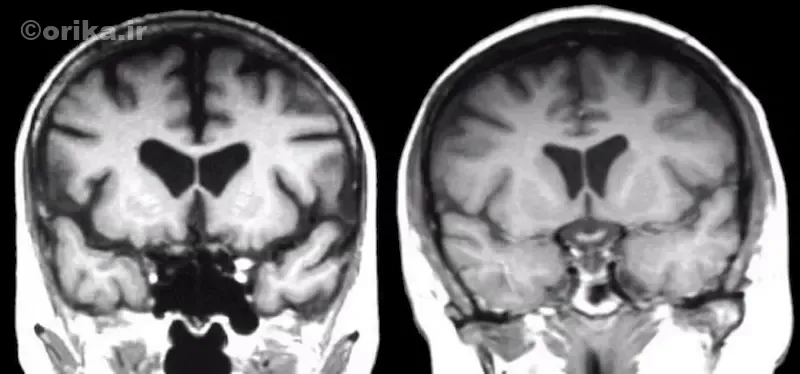

تخریب عصبی در مراحل اولیه از استریاتوم آغاز میشود؛ ناحیهای که در کنترل حرکت و احساس پاداش نقش دارد. در پی تحلیل تدریجی سلولهای این بخش، حرکات بدن از کنترل خارج میشوند. MRI نشاندهنده آتروفی هسته دمدار (Caudate nucleus) و بزرگشدن بطنهای جانبی است.

در مراحل پایانی، مغز بهطور قابل توجهی کوچک میشود و وزن آن تا ۳۰٪ کاهش مییابد. همبستگی مستقیم بین شدت آتروفی و تعداد تکرارهای CAG ثابت شده است.

پزشک متخصص مغز و اعصاب معمولاً از MRI و گاهی PET-scan برای بررسی آتروفی مغز استفاده میکند. در مراحل اولیه، تغییرات تصویری شامل باریکشدن استریاتوم و افزایش فضاهای بطنی است. مهم است که بیماریهای مشابه مانند HDL2، SCA17، Wilson و parkinsonism از هانتینگتون افتراق داده شوند. قطعیت تشخیص، فقط با تست ژنتیک مستقیم HTT CAG ممکن است.